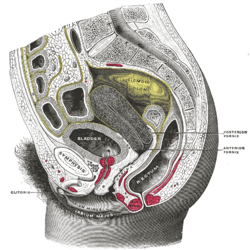

Anatomy of the bladder and outlet

The main organs involved in urination are the urinary bladder and the urethra. The smooth muscle of the bladder, known as the detrusor, is innervated by sympathetic nervous system fibers from the lumbar spinal cord and parasympathetic fibers from the sacral spinal cord.[4] Fibers in the pelvic nerves constitute the main afferent limb of the voiding reflex; the parasympathetic fibers to the bladder that constitute the excitatory efferent limb also travel in these nerves. Part of the urethra is surrounded by the male or female external urethral sphincter, which is innervated by the somatic pudendal nerve originating in the cord, in an area termed Onuf's nucleus.[5]

Smooth muscle bundles pass on either side of the urethra, and these fibers are sometimes called the internal urethral sphincter, although they do not encircle the urethra. Further along the urethra is a sphincter of skeletal muscle, the sphincter of the membranous urethra (external urethral sphincter). The bladder's epithelium is termed transitional epithelium which contains a superficial layer of dome-like cells and multiple layers of stratified cuboidal cells underneath when evacuated. When the bladder is fully distended the superficial cells become squamous (flat) and the stratification of the cuboidal cells is reduced in order to provide lateral stretching.